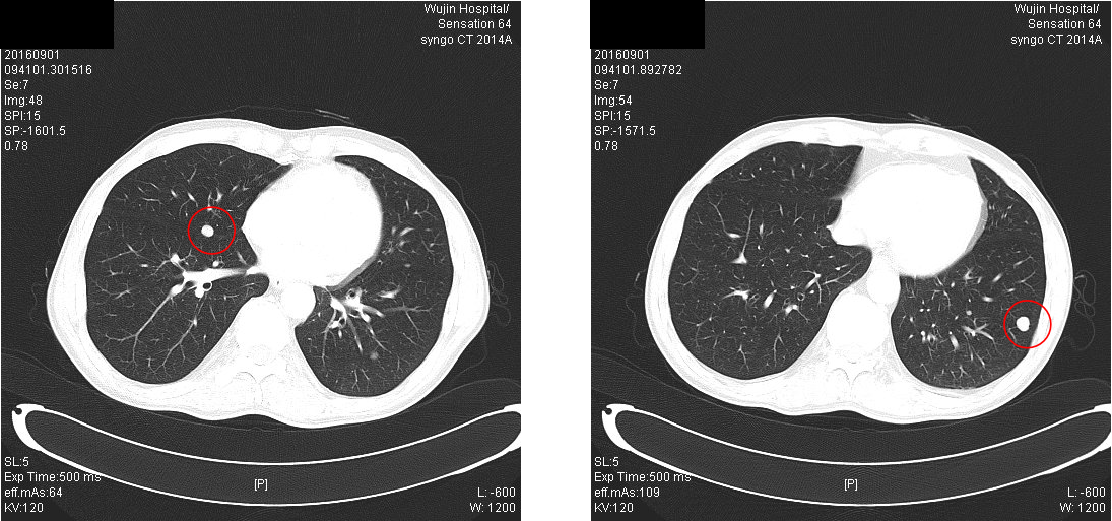

2016-09-01:

诊断:升结肠癌IV期(双肺多发转移)

2016-10-27胸腹部CT示:“1.结肠癌复查,升结肠局部肠壁增厚(结肠肝曲为著,肠壁增厚程度不及2016年9月1日片明显),周围多发小淋巴结;2.肝右后叶小血管瘤可能;3.前列腺偏大;4.直肠壁偏厚;5.两肺散在小结节,转移可能大(部分病灶较前稍增大);6.纵隔轻度肿大淋巴结”。

期间定期复查CEA、CA125、CA199均正常,定期复查胸腹部CT,综合评价病情稳定,但肺部病灶缓慢增大。